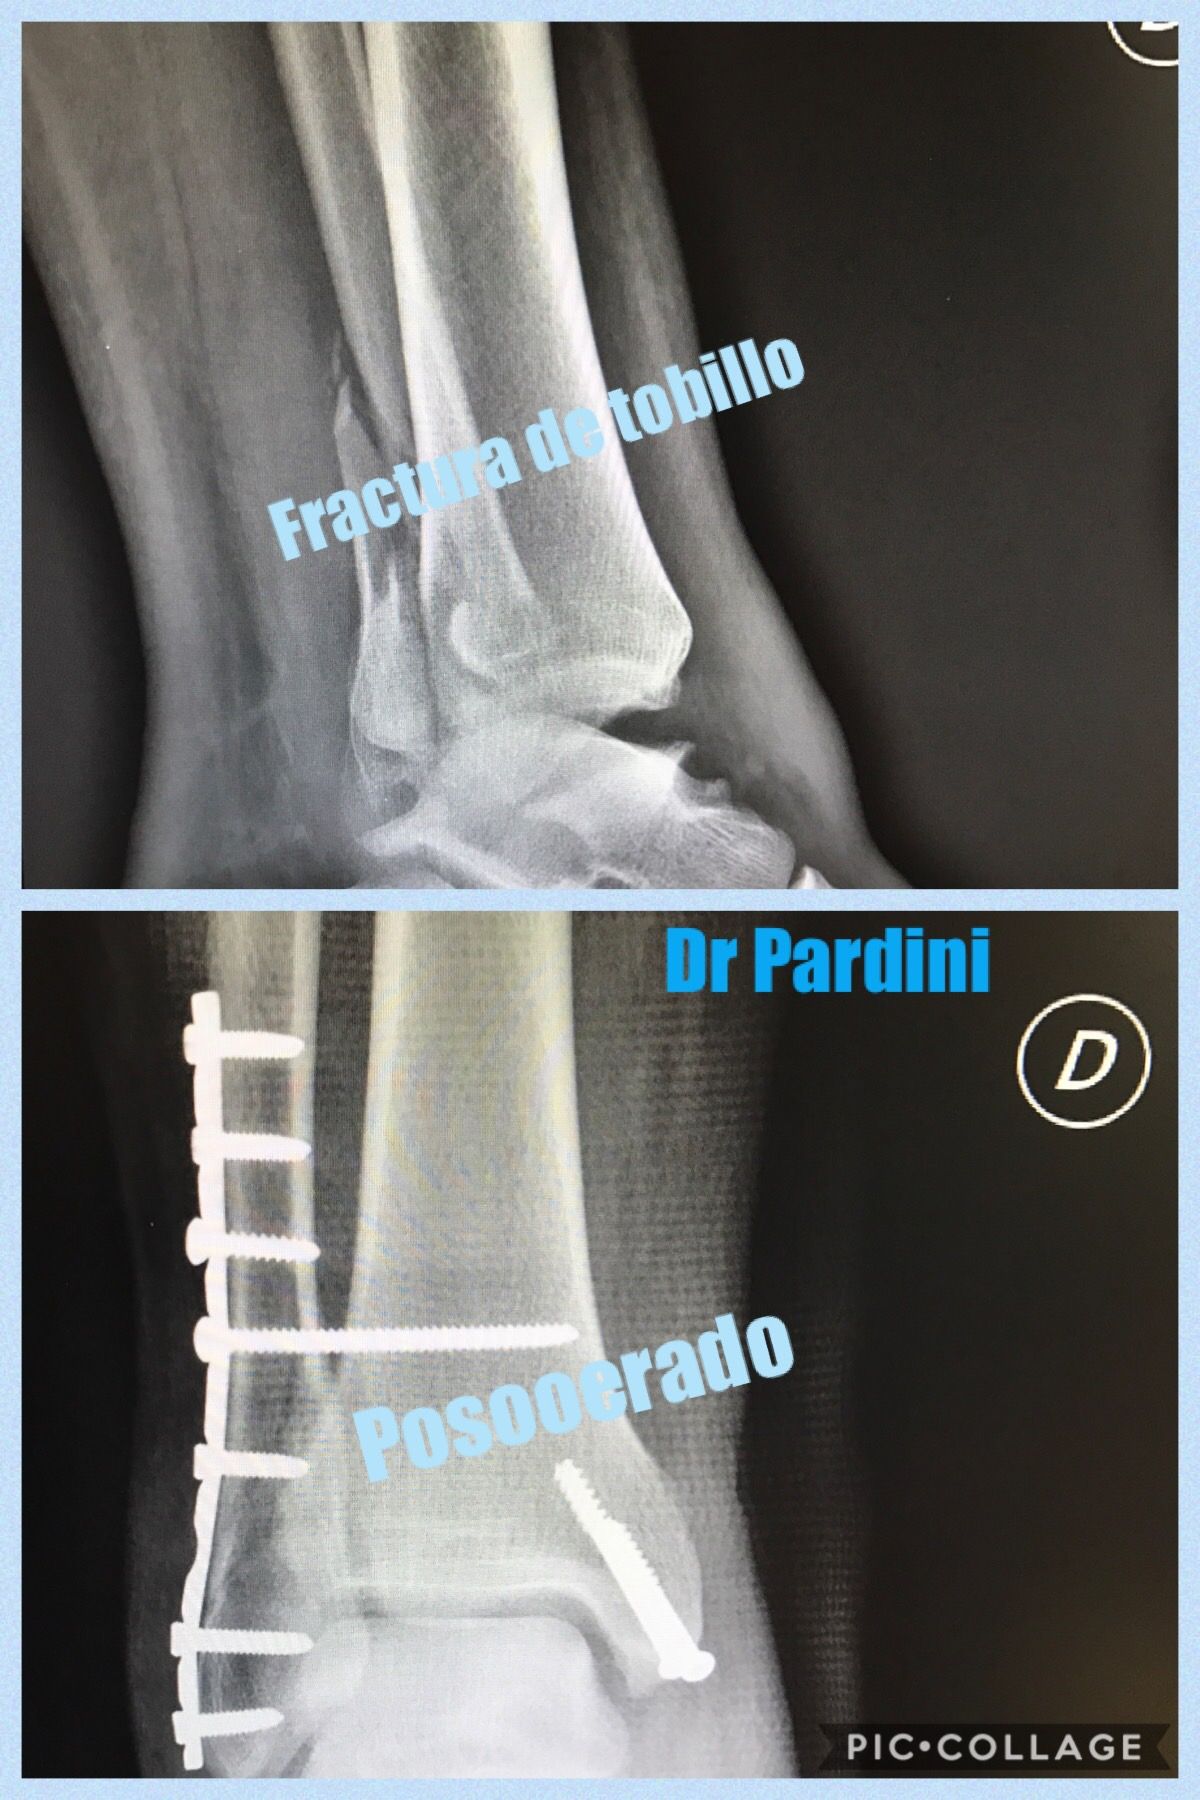

Duda sobre Fractura de tobillo y pie

Buenas tardes a mi hijo el 25 de enero lo operación del tobillo y dice que se atoca los tornillos es normal o algo esta mal con su operación

Buenas tardes¡¡

a veces es normal, depende de que tan delgada este la piel del paciente, si no duele no hay problema

saludos

Dr. Carlos Gpe. Pardini Angulo